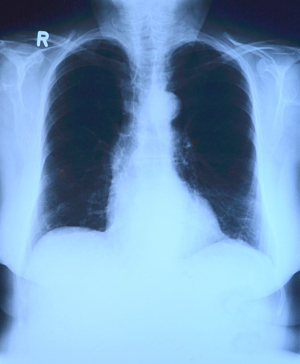

폐렴의 증상이 나타나면 X-선 촬영과 배양 검사로 진단할 수 있습니다. 상황에 따라 소변, 혈액, 혈청 검사, CT 등의 추가 검사가 필요할 수 있습니다. 폐렴 진단을 받은 환자 대부분에게는 입원 치료가 권장되지 않지만, 젊은 환자, 기저질환을 가진 환자, 호흡곤란이 심한 환자, 고령자, 임산부 등은 병원에서 치료를 받는 것이 좋습니다. 이를 통해 상황에 맞는 신속한 치료와 상태의 개선, 위험 요소의 관리가 가능합니다.